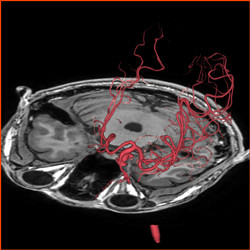

▲典型的脑动静脉畸形,

红色的为供血动脉及畸形血管团,蓝色的为粗大的引流静脉。

▲血管自动提取功能,

令供血动脉在杂乱的血管中一目了然。